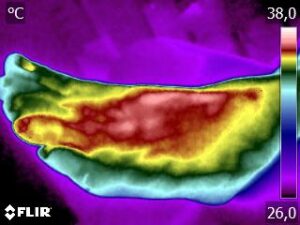

Como no caso da sequência de termogramas abaixo de uma paciente do sexo feminino, 51 anos e sem comorbidades e que sofreu um trauma de pé esquerdo durante a prática esportiva. Fez exame de Raio-X e não foi detectado fraturas, mas ainda apresentava muita dor. No 4º dia de pós trauma realizou uma Análise Termofuncional e foi detectado alterações térmicas condizente com processo inflamatório.

A terapia então foi ajustada para tratar esta lesão, não sobrecarregando a mesma e não apenas tratando a sintomatologia, mas sim até sua completa restauração.

Como no caso apresentado acima, a Termofuncional lhe proporciona não só “enxergar” as alterações térmicas, mas também uma maior segurança na terapia, com isso você poderá ter resultados muito mais eficazes. Além de lhe garantir segurança jurídica para cada procedimento que você realizar na sua reabilitação.